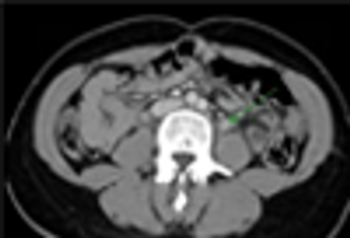

A 26-year-old man presented with sudden onset of palpitations and shortness of breath after incidentally taking tadalafil. He had no other symptoms and no history of illnesses during childhood. He drank socially but denied smoking and use of illicit drugs.